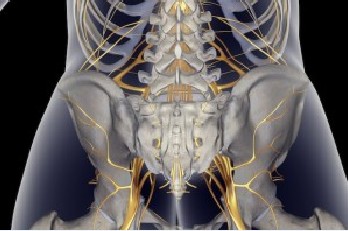

Kenali Gejala Nyeri Pinggang yang Disebabkan Saraf Terjepit

Kenali Gejala Nyeri Pinggang yang Disebabkan Saraf Terjepit

Sakit Pinggang Akibat Gangguan Syaraf, Ini Solusinya - Tribunnews.com Mobile

Sakit Pinggang Akibat Gangguan Syaraf, Ini Solusinya - Tribunnews.com Mobile